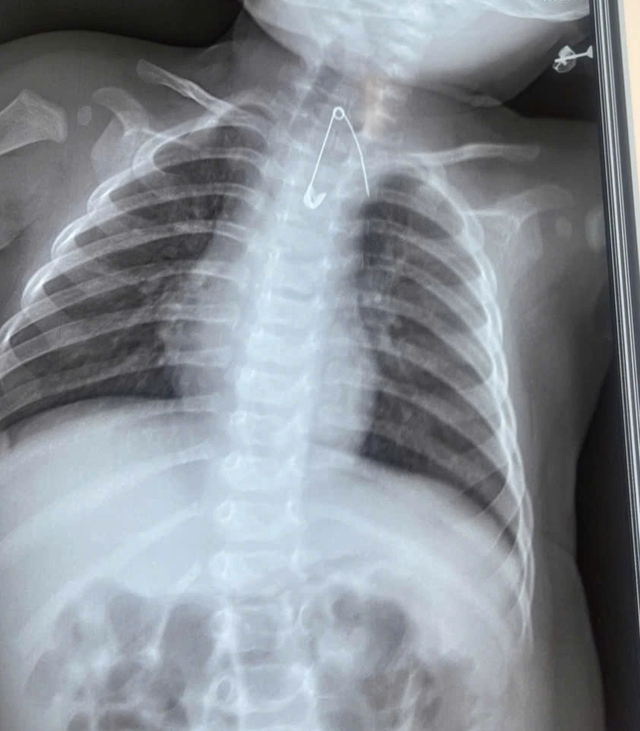

Trường hợp còn lại là bé trai T.B.Đ (7 tháng tuổi, ngụ xã An Trạch, Cà Mau), được người nhà đưa đến bệnh viện trong tình trạng sốt, ho và khò khè liên tục suốt 2 ngày. Qua khai thác bệnh sử, các bác sĩ ghi nhận trong khoảng 3 tháng gần đây, trẻ nhiều lần bị ho, viêm đường hô hấp và tái phát kéo dài. Gia đình cho biết có thói quen dùng kim tây ghim "bùa bình an" lên áo của bé.

Dị vật là kim ghim nằm trong mô mềm, ở vị trí đặc biệt nguy hiểm, sát động mạch chủ bệnh nhân T.B.Đ

ẢNH: BVCC

Qua thăm khám kết hợp các xét nghiệm cận lâm sàng, bác sĩ phát hiện dị vật là kim ghim nằm trong mô mềm, ở vị trí đặc biệt nguy hiểm, sát động mạch chủ. Dị vật này có nguy cơ gây tổn thương mạch máu lớn, dẫn đến xuất huyết ồ ạt và đe dọa trực tiếp tính mạng nếu không được can thiệp kịp thời.

Trước tình huống nguy cấp, ê kíp phẫu thuật nhanh chóng tiến hành lấy dị vật, xử trí an toàn, ngăn chặn những biến chứng nghiêm trọng có thể xảy ra.